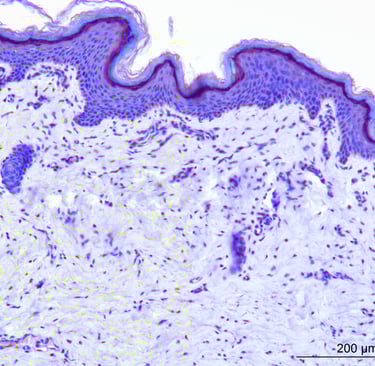

Antioxidant products aim to reduce damaging free radicals which can disrupt skin processes and increase the signs of ageing. Therefore, tests of these pathways are increasingly popular.